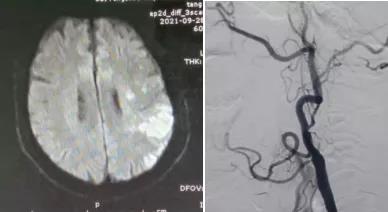

患者男,66歲,因“言語不清1天”于9月27日由外院轉(zhuǎn)入我院。既往“高血壓病”病史10余年,“冠心病心絞痛”病史2年。患者入院后頸部血管彩超檢查示:左側(cè)頸內(nèi)動脈閉塞;腦MRI檢查示:左側(cè)半球急性腦梗死。10月5日行全腦血管造影檢查示:左側(cè)頸內(nèi)動脈起始處閉塞。考慮患者有急性梗死,血管再通治療容易出現(xiàn)過度灌注綜合征引起腦出血,建議3周后行閉塞再通治療。

10月27日,在局部麻醉下行介入再通治療,腦血管造影示左側(cè)頸內(nèi)動脈起始處閉塞,微導(dǎo)絲攜1.5*2mm球囊多次嘗試,成功通過閉塞段,給予球囊擴張,擴張后造影見有細(xì)血流通過,保護(hù)傘緩慢通過狹窄段,釋放保護(hù)傘,給予4*20mm球囊再次擴張,然后植入閉環(huán)支架一枚,造影示血流通暢,顱內(nèi)血管顯影良好,再通成功,結(jié)束手術(shù),患者無不適,3天后出院。